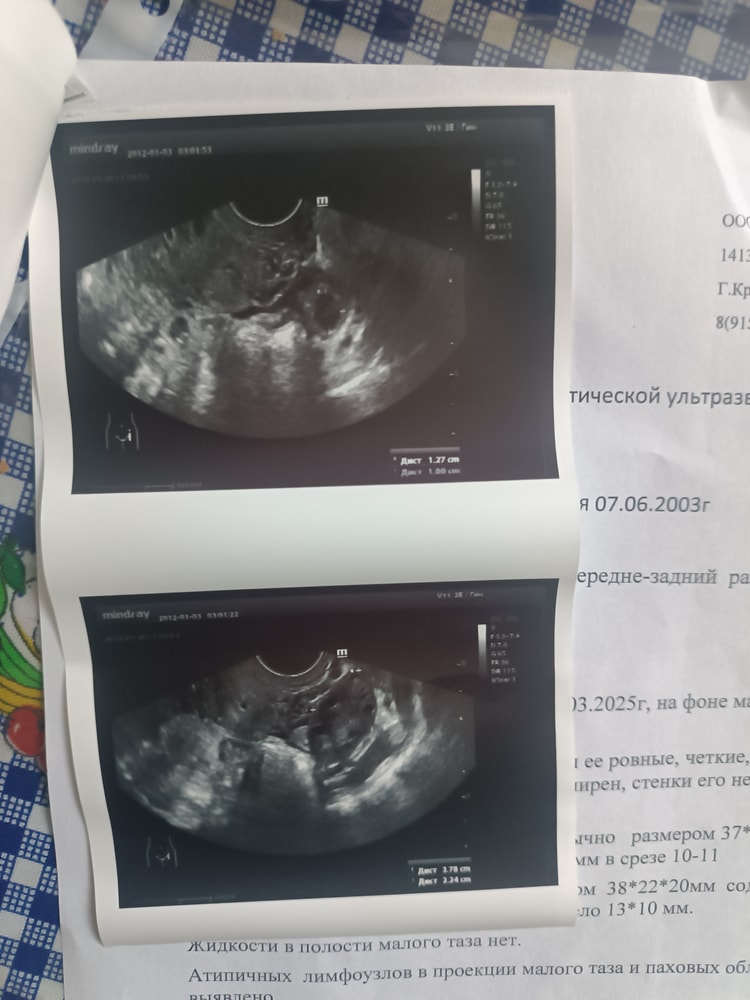

Очень пугает эта надпись мультифоликулярные яичники

Прекрасные яичники, хороший запас. Даже не парьтесь. Радуйтесь) мне только одна додумалась написать про мультифолликулярные яичники, и до нее никогда такого диагноза не было. Главное чтоб была овуляция, ну и может цикл быть не 28, а до 30-31. Вот и всё особенности.

Это не диагноз и ничего по сути не значит, просто наблюдение УЗИ. У вас хороший овариальный запас, все.

Это не диагноз, а особенность строения яичников

На зачатие беременность никак не влияет, если овуляция своя есть

МФЯ - это яичники с большим запасом, когда около 20 филликулов в каждом при фолликулометрии. Это скорее хорошо, чем плохо. Но рядом с МФЯ стоит СПКЯ, тут уже немного другие прогнозы. При СПКЯ может овуляция быть через раз и цикл не стабильный. А без постоянной овуляции действительно забеременеть чуть сложнее.